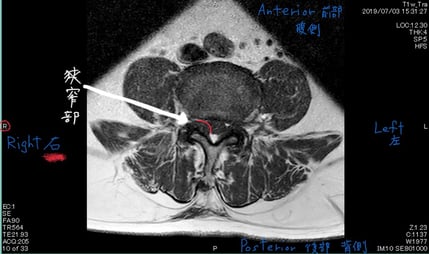

狭窄部と症状側が同じ

脊柱管 上関節突起 骨棘 椎間板変性

整形外科にてレントゲン、MRI検査をし脊柱管狭窄症と診断。牽引、電療、投薬治療にて改善せず来院される。